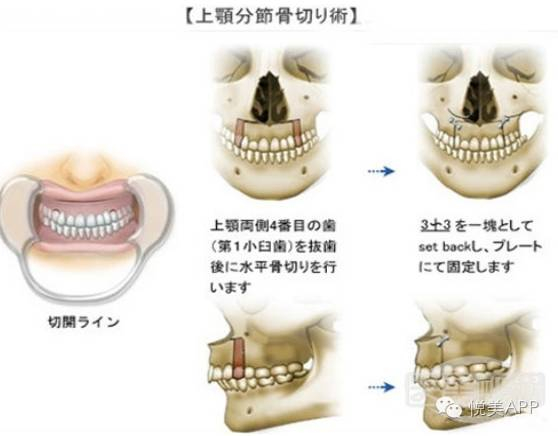

第二步:正颌外科手术,将长出来的部分骨头切除,然后往回推,固定住,形成正确咬合状态~

第二种:上颌骨截骨术——针对上颌后缩导致,将上上颌骨整体前移,改善面中部凹陷,如果矫正后鼻部较低,还可以配合隆鼻手术。